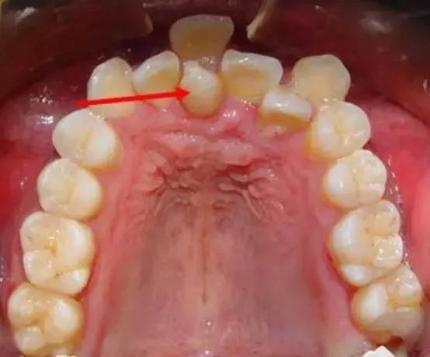

多生牙又称额外牙,是正常牙列以外的多余牙齿,是多于正常牙数以外的发育异常的牙齿。在形态上,其多为锥形牙或者过小牙,也可与正常牙齿形态相似。在数量上,可分为单发或者多发。在位置上,可分为正中、前磨牙区、磨牙区等,其中上颌前牙区最为常见。在空间上,可萌出在口腔,一般口内检查可见;也可埋伏阻生,只能通过X线检查发现。

多生牙往往没有临床症状,多在拍片时偶然发现。但其危害不容忽视,可影响恒牙的发育,可引起恒牙的迟萌或者阻生,恒牙牙根形态发育异常,出现牙间隙、牙齿扭转或者移位。多生牙可能横着、倒着、斜着埋伏在颌骨里占据正常牙齿的位置,从而影响恒牙的萌出。甚至,久而久之,多生牙阻挡恒牙牙根正常生长方向,导致恒牙牙根弯曲。此外,多生牙也可以在乳牙脱落前后萌出,临床上我们看见形态不正常的牙齿或者牙尖。萌出的多生牙占据了正常恒牙在牙列中的位置,造成牙列不齐。

1 牙列拥挤

2 牙齿移位

3 牙间隙大